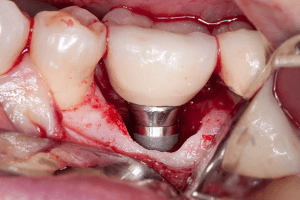

ایمپلنت ها از سه جز اصلی شامل فیکسچر، اباتمنت و روکش دندان تشکیل شده اند. فیکسچر یک پایه اصلی است که درون فک قرار می گیرد. درباره اباتمنت باید بگوییم که رابطی بین روکش ایمپلنت و فیکسچر می باشد. در واقع به کمک این قطعه می توان روکش را به راحتی به پایه یا فیکسچر آن متصل کرد. تاج یا روکش ایمپلنت که ظاهری ترین قسمت ایمپلنت است کاملاً متناسب با رنگ دندان های فرد بر روی ابانمتت قرار می گیرد. حال اگر بدن فرد به هر دلیلی از دلایل مذکور در متن فوق ایمپلنت را نپذیرد و آن را پس بزند فرد علائمی را در داخل دهانش احساس خواهد کرد.

- اگر التهاب به بافت های پریودنتال عمیق گسترش یافته باشد، لثه بریده می شود. تمام کانون های عفونت و گرانول ها برداشته می شوند. یک دوره آنتی بیوتیک تجویز می شود.

- اگر عفونت به بافت های استخوانی گسترش یافته باشد، ایمپلنت باز می شود. بافت های سخت و نرم آسیب دیده برداشته می شوند. زخم ضد عفونی می شود. داروهای ضد التهاب و ضد باکتری تجویز می شود. پس از فروکش کردن التهاب، ماده استخوان مصنوعی پیوند زده می شود. کاشت مجدد فوری انجام می شود که به بیمار اجازه می دهد در عرض یک روز ایمپلنت های جدید دریافت کند.